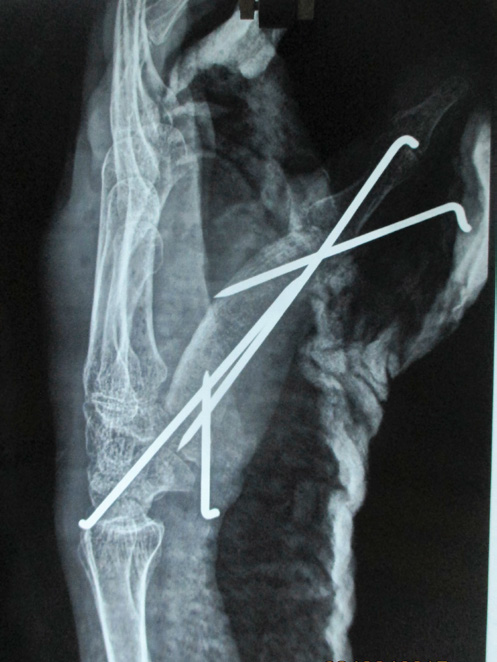

In November 2015 one 60 years lady presented in a newly recognised Medical College of eastern India (Murshidabad Medical College) with recurrence of GCT of the 1st MC of left hand and soft tissue involvement. One year back she was presented in another medical college with intraosseous Capancci grade III lesion of the same site of two years duration where it was treated with narrow margin resection, interposition bone cement on a Kirschner wire (K wire) (Figure 1). It started recurring after 8 months of resection. But presented to us after another one year when extensive extension within soft tissue took place. In plain x ray one small osteolytic lesion was noticed over mid shaft of second metacarpal of the same hand which was not seen in earlier radiographs. MRI was done to identify adjacent bone involvement and to know extent of the lesion in soft tissue (Figure 2). Involvement of regional lymph node and lung metastasis were excluded clinically and radiologically.

Figure 1 a. Initial X-ray initial presentation 3 years back; post-operative X-ray after initial operation; b. immediate; c. subsequent.

Under tourniquet control and regional anaesthesia through dorsoradial incision the mass along with bone cement was removed, meticulously cleaning of original tumour site was done. Excised tissue was preserve for histopathology (HP). With a separate set of clean instrument the osteolytic area second metacarpal was curetted and the material is preserved in separate jar for HP study. Tricortical bone graft from iliac crest of appropriate size was harvested and placed in position with 4 K-wires. After closure of wound hand and forearm was placed in plaster of Paris slab. Stitches were removed after 2 weeks but cast continued for 2 months and K wires continued for 3 months when graft ends started uniting and partially incorporated (Figure 3). Histopathology reported as GCT without malignancy from both the specimens. 75 % movements of carpometacarpal and metacarpo-phalangeal joints were restricted but interphalangeal joint exhibit 50% motion (Figure 4). Wrist became free. In 1 year 3 months follow up there is no evidence of recurrence or metastasis. Considerable amount of reactive consolidating bone formation around 2nd MC radiologically.